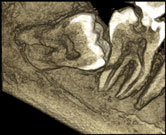

As part of the Planemica CT Scan, it has a direct deposit CSI semiconductor flat panel. This produces accurate, distortion-free images for 3D reconstruction. Unlike having an image intensifier sensors that use old vacuum tube technology and multi-step focusing, flat panels use single step image readouts. This means that there is no geometric distortion, no loss of sensitivity, and therefore no need for frequent calibration yet providing accurate imaging.

Planmeca ProMax 3D concept is expressly designed to comply with the needs of modern surgical dentistry. The 3D CT Scan unit complies with a multitude of diagnostic requirements including endodontics, periodontics, orthodontics, implantology, dental and maxillofacial surgery, and TMJ analysis. With all the Planmeca ProMax 3D models CT machine, study volume sizes are selectable to meet diagnostic needs without excess radiation outside the area of interest.

The Planmeca Romexis 3D Explorer, the 3D dental scan imaging acquisition software for Planmeca ProMax 3D CT Scan machine, enables flexible viewing in all three relevant projections: axial, coronal, and sagittal. The software incorporates a re-slicing feature, which enhances the projections and enables real-time three-dimensional viewing in the desired angle. A rendered 3D view provides a realistic overview of the anatomy.